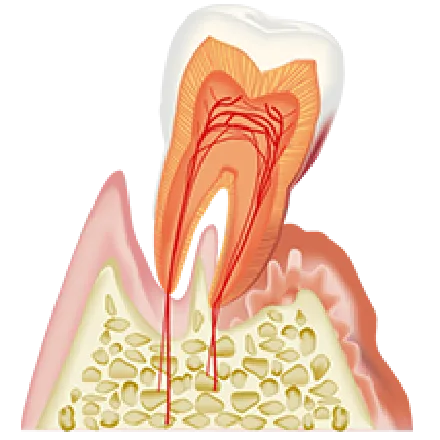

進行重度

歯の隙間が更に広がり、出血や膿、最悪の場合歯が抜け落ちる

気づかない内に進行するので放っておくと歯を失ってしまう恐れも

自覚症状の少ない歯周病は放置されることが多く、

「気づいたときには歯がグラグラになっていた」と

言う方も少なくありません!